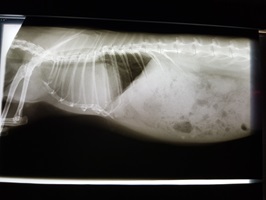

Ein Kaninchen mit Atembeschwerden oder den beschriebenen Augenveränderungen sollte zunächst geröngt werden. Hierdurch lassen sich Verschattungen im Brustkorb schnell und einfach erkennen und es muss anschließend nur noch ermittelt werden, ob es sich dabei um einen Tumor oder eine (reine) Herzerkrankung handelt. Letztere kann zu einem vergrößerten Herzen oder einem Erguss führen, was per Röntgendiagnostik nicht immer von einem Tumor zu unterscheiden ist.

Besteht eine entsprechende Verschattung, ist ein Herzultraschall angezeigt. Dabei können das Gewebe und die Herzfunktion eindeutig beurteilt werden. Dies ist auch deshalb von Bedeutung, da die Herzfunktion durch einen benachbarten Tumor beeinträchtigt werden kann. In diesem Fall muss das sekundäre Herzproblem in die Tumortherapie miteinbezogen werden.